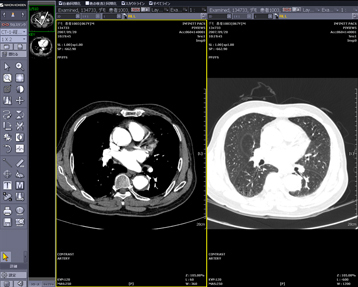

ハンギングプロトコルとは,ユーザーの読影目的に合わせ,画面構成をカスタマイズする機能のことです。モダリティや検査部位,ツールバー,サムネイルまで画面構成を設定することが可能です。過去画像比較(図4)や縦隔・肺野比較(図5),マルチモダリティ表示(図6)や3D画像作成機能(図7)までもがワンクリックで意図した画面レイアウトで表示され,迅速で簡単な読影環境を提供します。ハンギングプロトコルの設定は,ユーザーごとの設定であるため,ハンギングプロトコルをフル活用することにより,自分だけのオーダメイドPACSとして使用することができます。

![]() 図5 縦隔・肺野比較表示 |